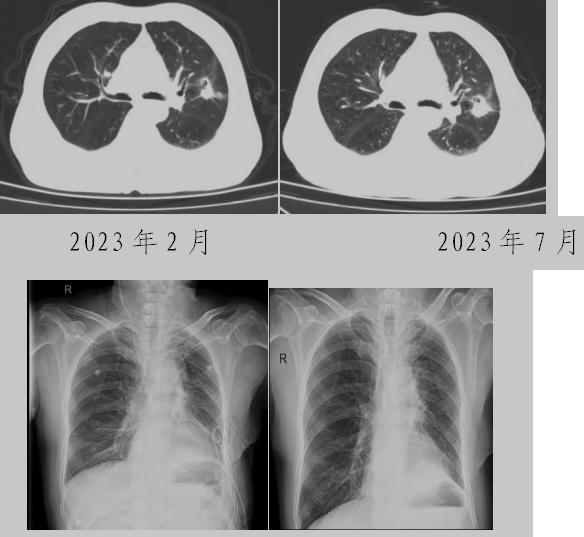

病例一:70多歲的患者王先生于2020年“急性心梗”入院時檢查發現了肺部結節,王先生沒有在意,其間未規范復查胸部影像學檢查,于2023年2月份再次發作心絞痛時,發現肺結節已發展成直徑約2.5cm實性腫塊,患者在家長期口服“替格瑞洛及腸溶阿司匹林”等抗凝藥物,生活可自理,于冠狀動脈二次植入支架后三個月,收住市二院胸外科,經心內科、麻醉科等多學科會診后,由胸外科主任王松陽、副主任醫師薛飛及科室團隊行“單孔胸腔鏡下左上肺癌根治術”,術后結合快速康復理念,三天后拔除胸管,一周出院。